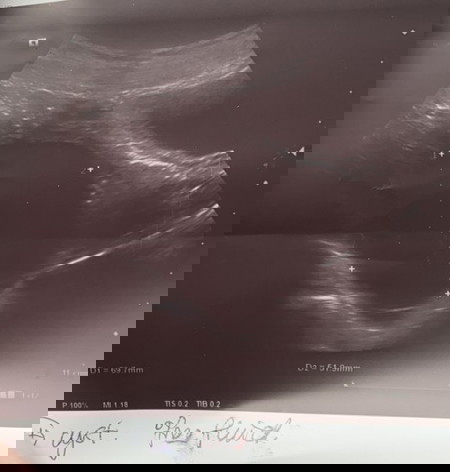

Cyst Besar Pada Awal kehamilan

Saya baru lepas scan baby , baby saya baru 5 weeks tapi saya dapat tahu saya ade cyst macam ni , doctor kata tak bahaya cuma doctor cakap kalau dia pecah & terbelit mungkin bahaya . so patut ke saya operate sebab takut effect nanti perut dah besar ? Sebab sekarang cyst tu sakit je , bila nak bangun sakit nak jalan pun sakit je 😢 #pleasehelp #1stimemom #advicepls